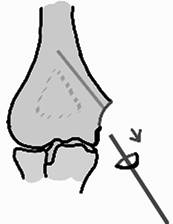

Perforación central del fragmento del epicóndilo medial con la guía de 1.25 mm del tornillo canulado de adentro hacia afuera (desde el foco de la fractura hacia la porción externa) (Figura 3).

Inserción de la guía desde la porción externa del epicóndilo hacia la interna (Figura 5).

Avance de la guía hacia la metáfisis del húmero en el sitio previamente perforado (Figura 6).

Reducción automática del epicóndilo (Figura 7).